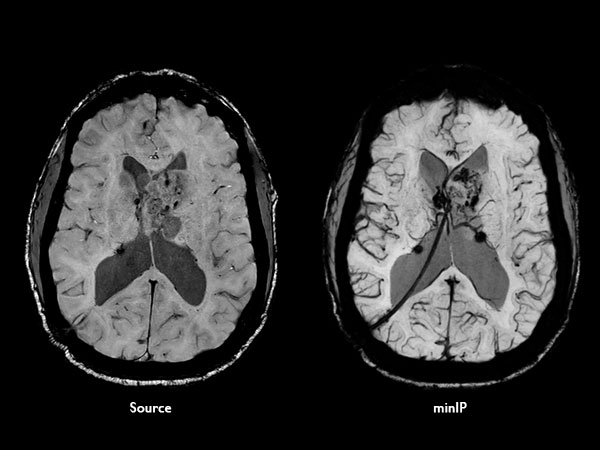

Axial SWIp